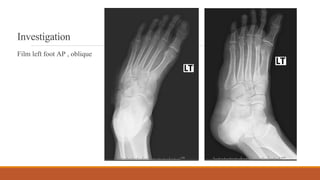

Investigation

Film left foot AP , oblique